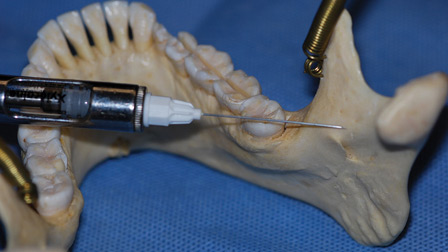

B.C. Expands PPEP Assessments to Include Anesthesia in Dental Facilities

The College of Physicians and Surgeons of BC (CPSBC) is expanding their Physician Practice Enhancement Program (PPEP) to anesthesiologists and those providing family practice anesthesia (FPA) in dental facilities for 2024. This means that those providing sedation and general anesthesia services may be required to complete a practice environment assessment and peer assessment. PPEP is an educational … Read more